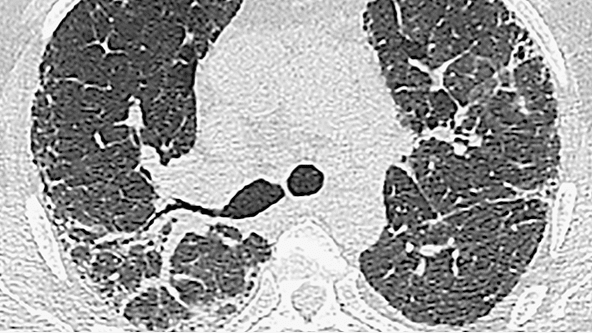

BRONȘIECTAZII DE TRACȚIUNE / BRONHIOLECTAZII

Caracteristici

• Dilatarea anormală și neregulată a bronhiilor/bronhiolelor din cauza inflamației tractului respirator (uneori reversibilă) sau a fibrozei pulmonare

• La scanarea HRCT, apare ca o creștere a calibrului tractului respirator distal (fără reducerea diametrului periferic, vizibilă pulmonar subpleural la cel puțin 20 mm de pleură)

• La scanare, se prezintă ca spații de aer tubulare sau chistice în funcție de orientarea bronhiilor în secțiune transversală.

• Diferențierea între bronșiectaziile de tracțiune și aspectul de fagure de miere este uneori dificilă pe secțiunile transversale axiale. Secțiunile transversale sagitale sau coronale și minIP sunt cele uzuale.

Diagnosticul orientativ

• Bronșiectaziile de tracțiune sunt asociate cu semne de fibroză

BRONHIOLECTAZIE

Bărbat de 72 de ani cu UIP. HRCT evidențiază reticulații difuze și bronșiolectaze și bronșiectazii de tracțiune.